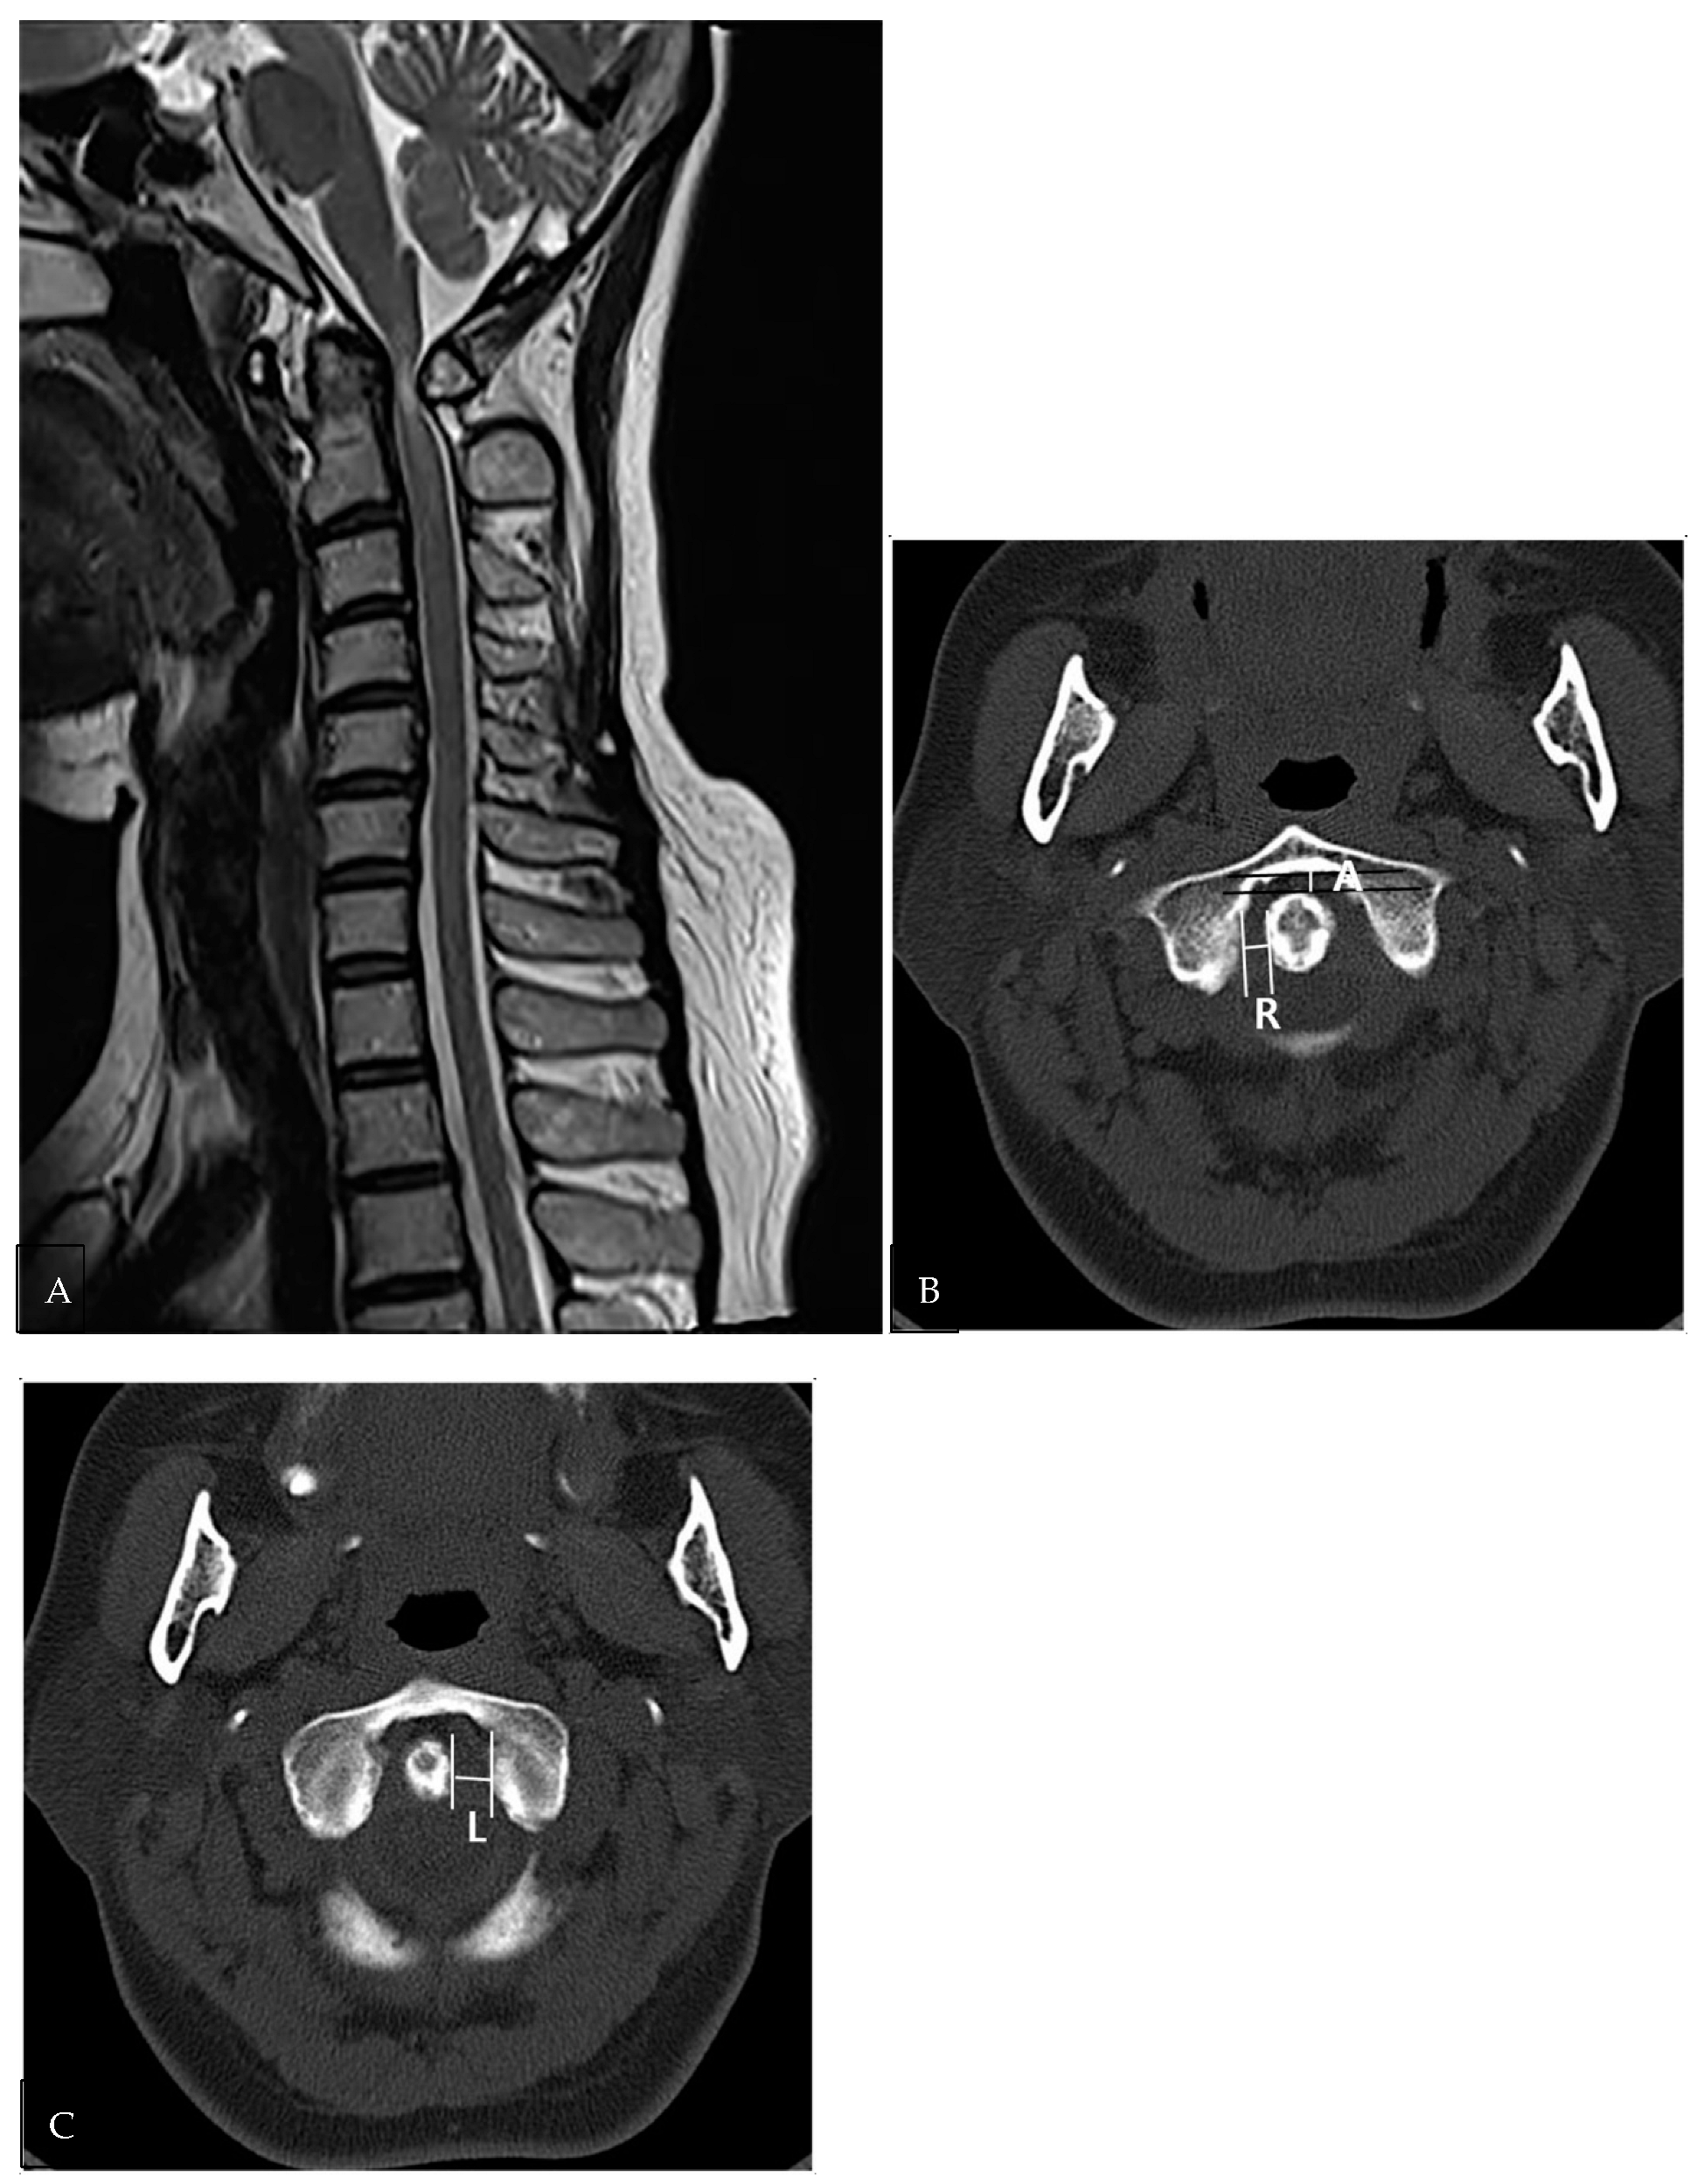

| Atlantoaxial instability on CT images | |||

| Right gap | 2.63 ± 1.5 (0.9–6.5) | 4.66 ± 1.88 (2.6–8.4) | 0.001 |

| Central gap | 2.1 ± 1.15 (0.67–4.7) | 5.18 ± 2.03 (2.4–10.1) | <0.0001 |

| Left gap | 2.87 ± 1.63 (0.9–7.93) | 4.51 ± 1.88 (1.6–7.2) | 0.005 |

| Difference between bilateral sides | 1.07 ± 1.22 (0.1–4.7) | 1.2 ± 1.09 (0.2–4.8) | 0.706 |